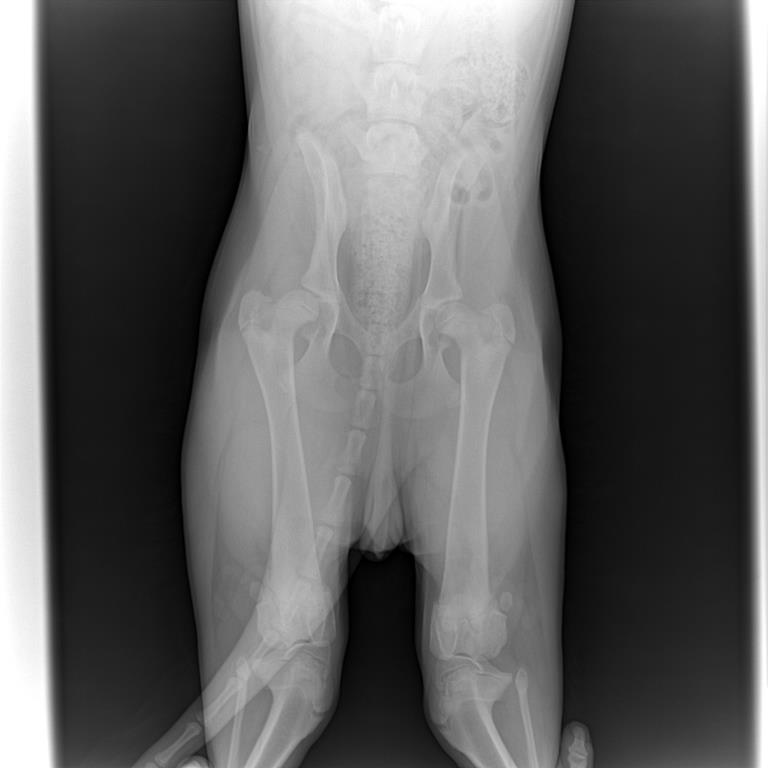

Здравствуйте! Подскажите пожалуйста,что делать. Взяли щенка немецкой овчарки в возрасте одного месяца. Все было хорошо. Когда хотели отдать на дрессировку нам сказали проверить ножки на дисплазию. Снимок делали в 4,5 месяца.Врач поставил дисплазию. В таком возрасте можно ставить точный диагноз? К сожалению снимки не подписали.

Вложения

124722_0harvi.jpg

124725_01harvi.jpg

То,что видно по снимкам-дисплазия имеется. Но лечение и указания должен назначать врач,учитывая состояние собаки и наличие или отсутствие других симптомов.

Насчет возраста-обычно с возрастом становится хуже,а не наоборот.